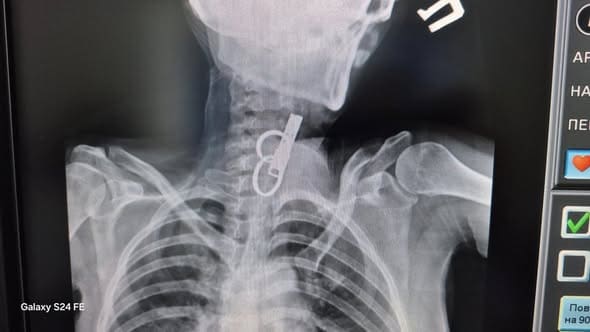

У Гусятині на Чортківщині лікарі успішно видалили зі стравоходу 40-річної жінки дверний ключ. Медичне втручання провели без хірургічного розрізу – за допомогою ендоскопічного обладнання. Про це повідомили у КНП «Гусятинська комунальна лікарня».

За інформацією медиків, пацієнтка проковтнула ключ навмисно – з особистих мотивів. До лікарні вона потрапила у шоковому стані. Після обстеження лікарі оперативно встановили причину та ухвалили рішення про невідкладне втручання.

Завдяки наявності сучасного ендоскопічного обладнання стороннє тіло вдалося видалити без відкритої операції.